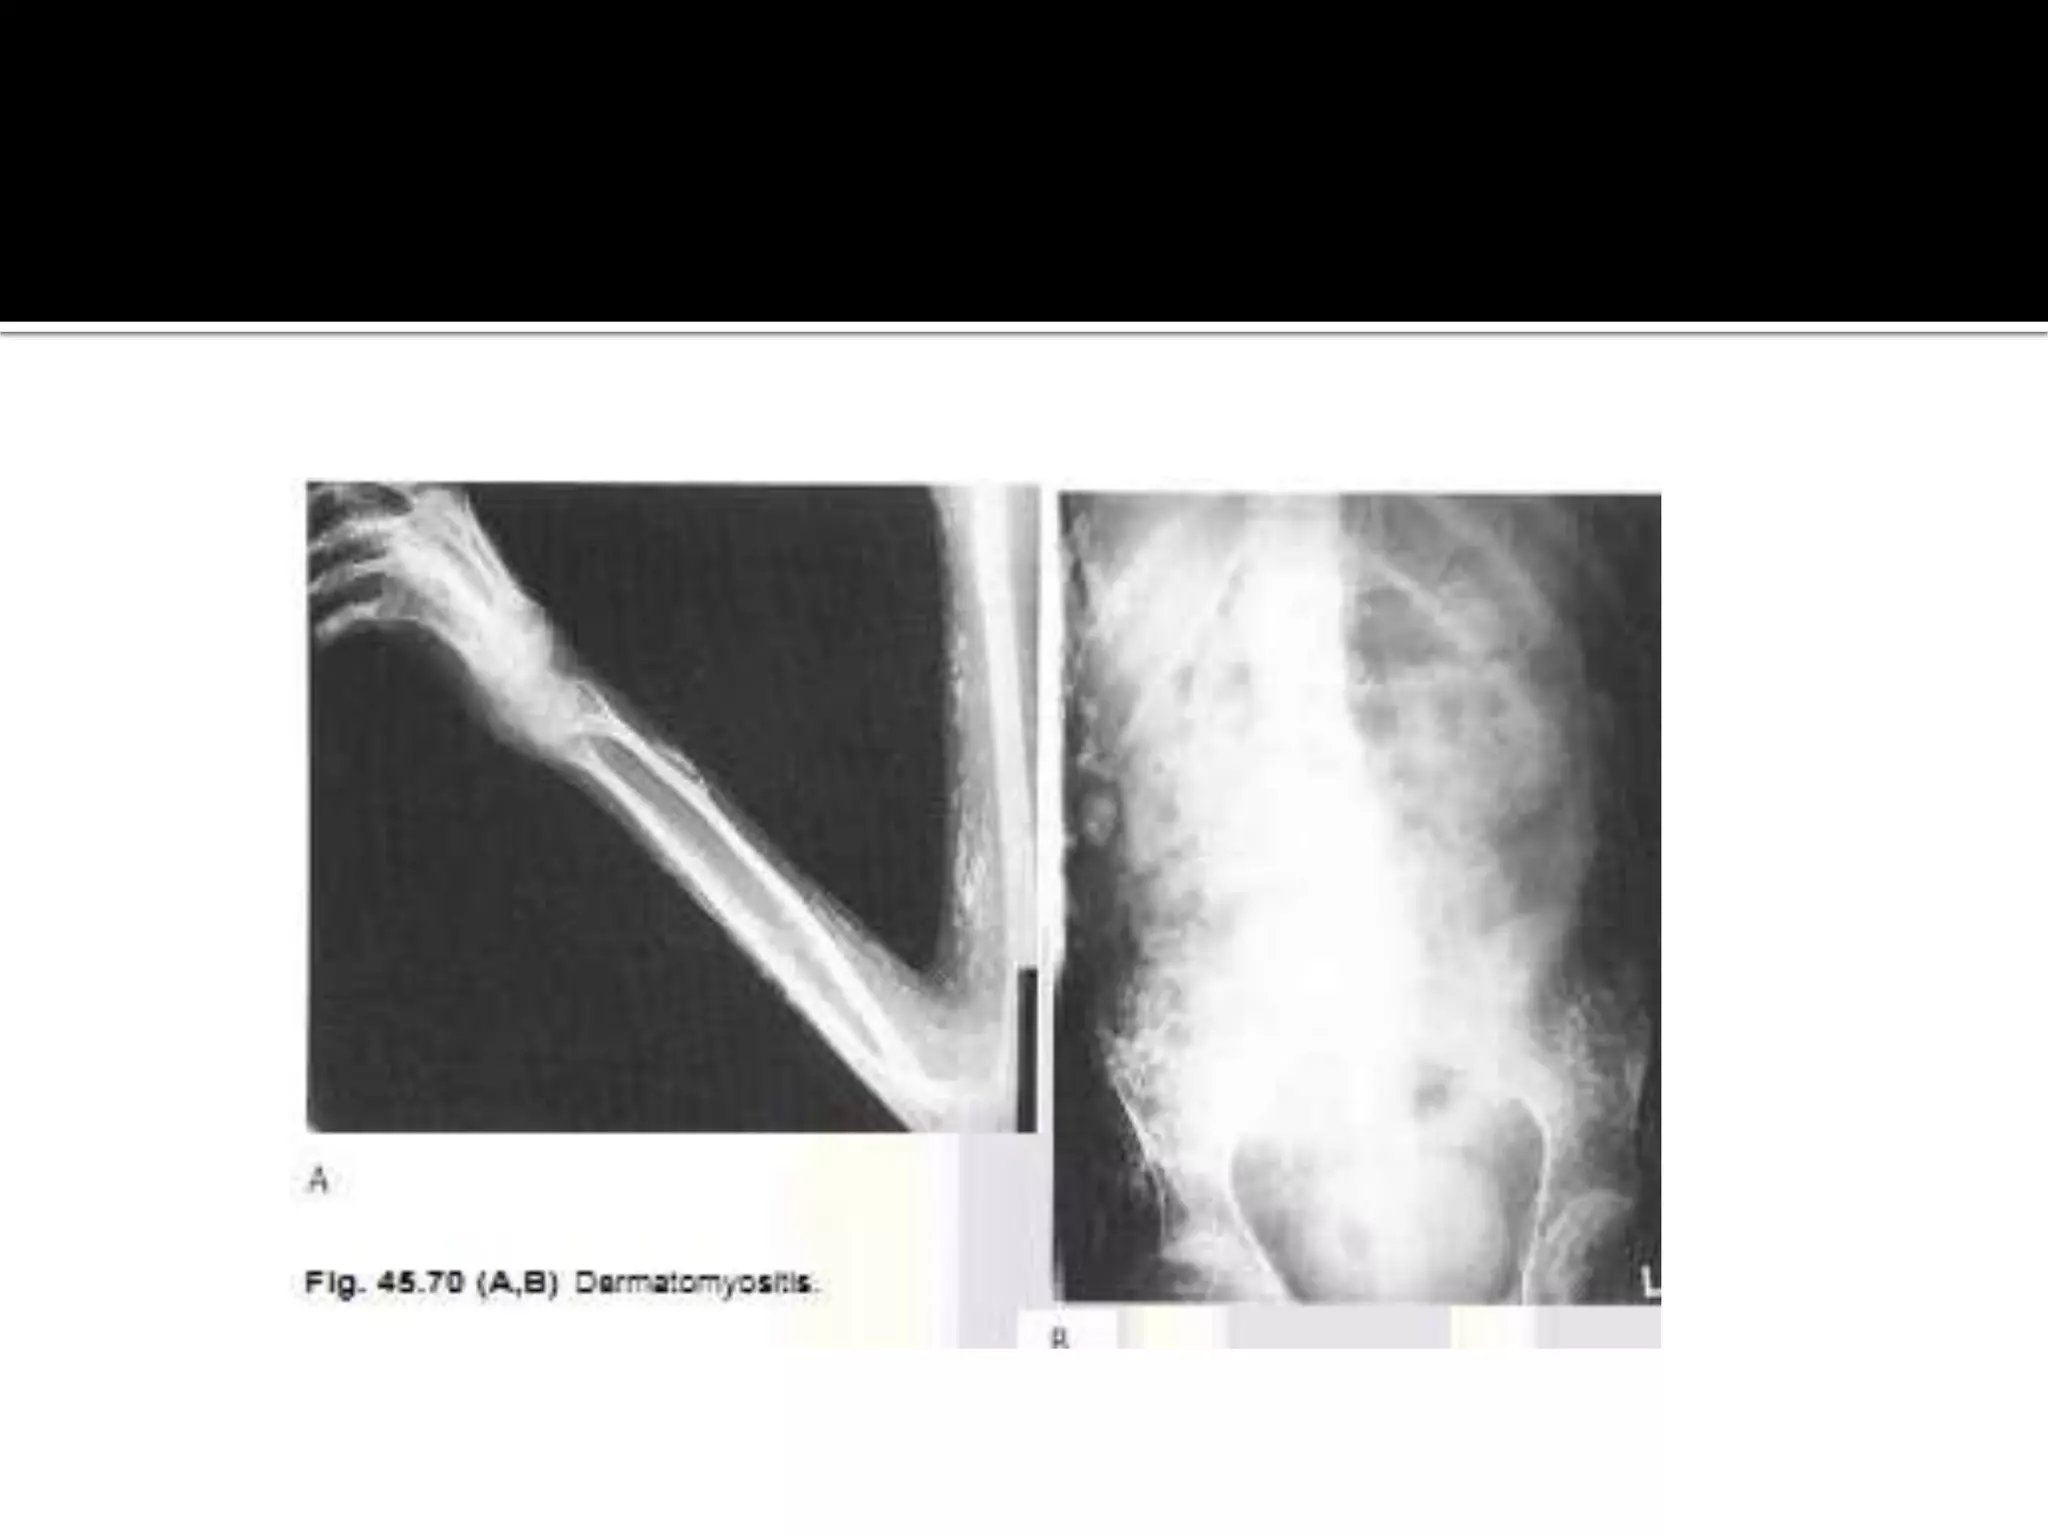

Calcinosis interstitials universalis or

dermatomyositis.

there is degeneration of the collagen tissue resulting

in diffuse subcutaneous plaques or nodules of

calcium or reticular calcification often with

overlying ulceration . In addition with progression

,calcified masses or sheets of calcium form in the

deeper tissues and lie in the direction of the limbs.

 There is normal calcium and phosphate metabolism

 those affected have pain and muscle weakness

 if progressive the disease may be fatal. In adults

there is an association between dermatomyositis

and malignancy.

Calcinosis interstitials universalisor dermatomyositis. there is degeneration of the collagen tissue resulting in diffuse subcutaneous plaques or nodules of calcium or reticular calcification often with overlying ulceration . In addition with progression ,calcified masses or sheets of calcium form in the deeper tissues and lie in the direction of the limbs.

• 38.

 There isnormal calcium and phosphate metabolism  those affected have pain and muscle weakness  if progressive the disease may be fatal. In adults there is an association between dermatomyositis and malignancy.  Ehler,s Danlos syndrome is hereditary disorder with findings including lax joints ,fragile and elastic skin and blood vessels ,acro osteolysis and subcutaneous nodules